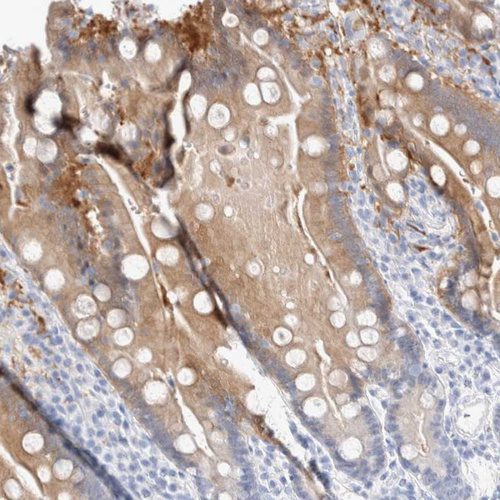

Immunohistochemistry analysis in human cerebral cortex and skeletal muscle tissues using HPA024099 antibody. Corresponding GDA RNA-seq data are presented for the same tissues.